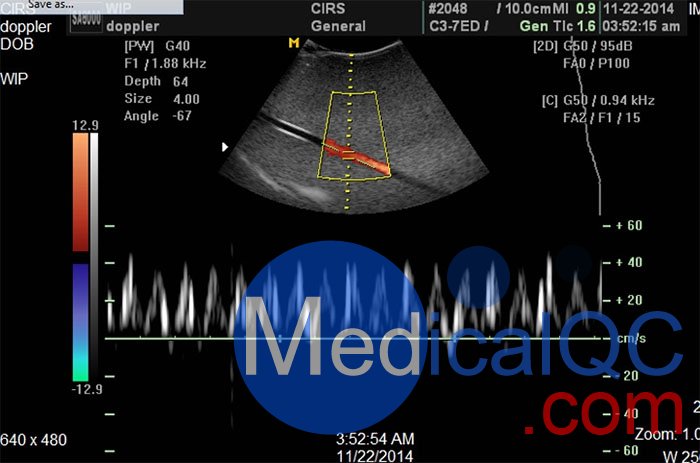

多普勒超聲圖像與多普勒超聲波流量模體顯示脈動和連續流動。